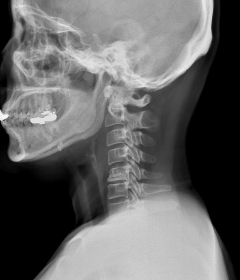

정상적인 목뼈는 C자 형태의 굴곡을 지니고 있습니다. 이를 "전만"이라고 합니다.

그러나 잘못된 자세나 생활습관으로 인해 목뼈의 모양이 일자로 곧게 뻗은 경우는 '일자목 증후군'이라고 하며, 더 심한 경우는 반대 C자 형태 즉, 역 C자 형태의 목을 '거북목 증후군' 또는 '자라목 증후군'이라고 합니다. 이는 의학적으로 경추 후만증으로 일컫습니다.

거북목

일자목